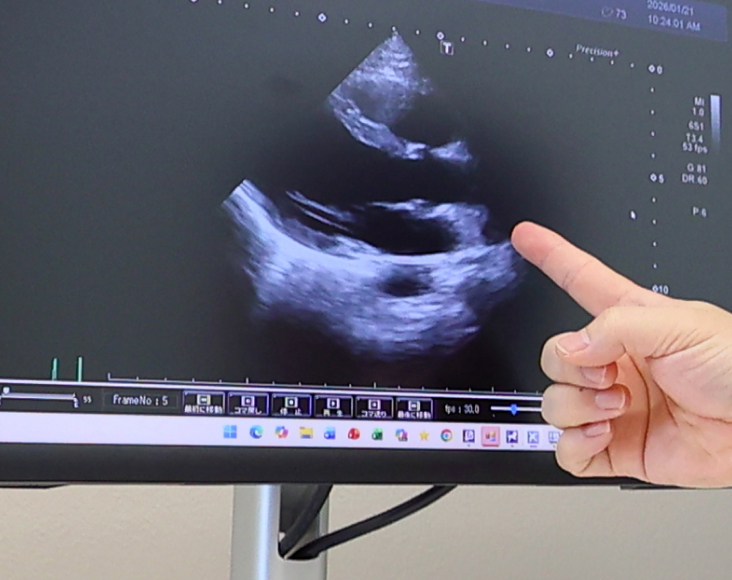

日本循環器学会認定の循環器専門医が、最新のガイドラインに基づいた高度な診療を行います。心エコーやBNP検査を駆使して正確に病態を把握し、患者様一人ひとりの心機能に合わせた最適な薬物療法を提供します。

心臓リハビリは、医師が心エコーやBNP検査などで病態を正確に把握し、安全な運動強度を設定した上で行います。専門スタッフが血圧や心拍数、体調の変化を常にチェックしながら実施するため、ご自身で運動するよりも安全に体力をつけることが可能です。万が一、運動中に胸の痛みなどの異変があった場合も、その場ですぐに医師による適切な治療介入ができる体制を整えています。